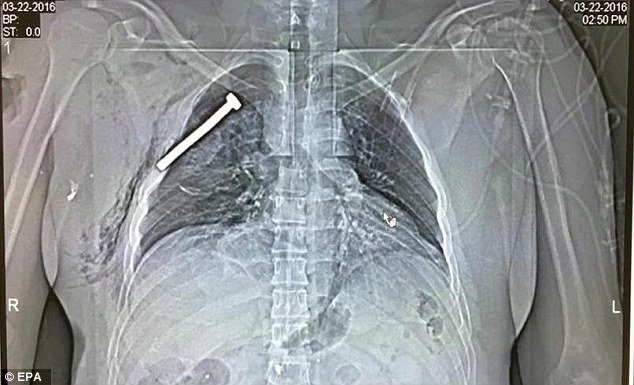

MailOnline twitterde op dinsdag 22-03-2016 om 18:33:13 X-ray shows a NAIL lodged next to #Brussels bombing survivor’s heart https://t.co/1pWepbR8KE https://t.co/vVpfsQibyu reageer retweet

quote:

0s.gif Op dinsdag 22 maart 2016 18:46 schreef YazooW het volgende:

[ afbeelding ]

:o :{

wat een barbarij.